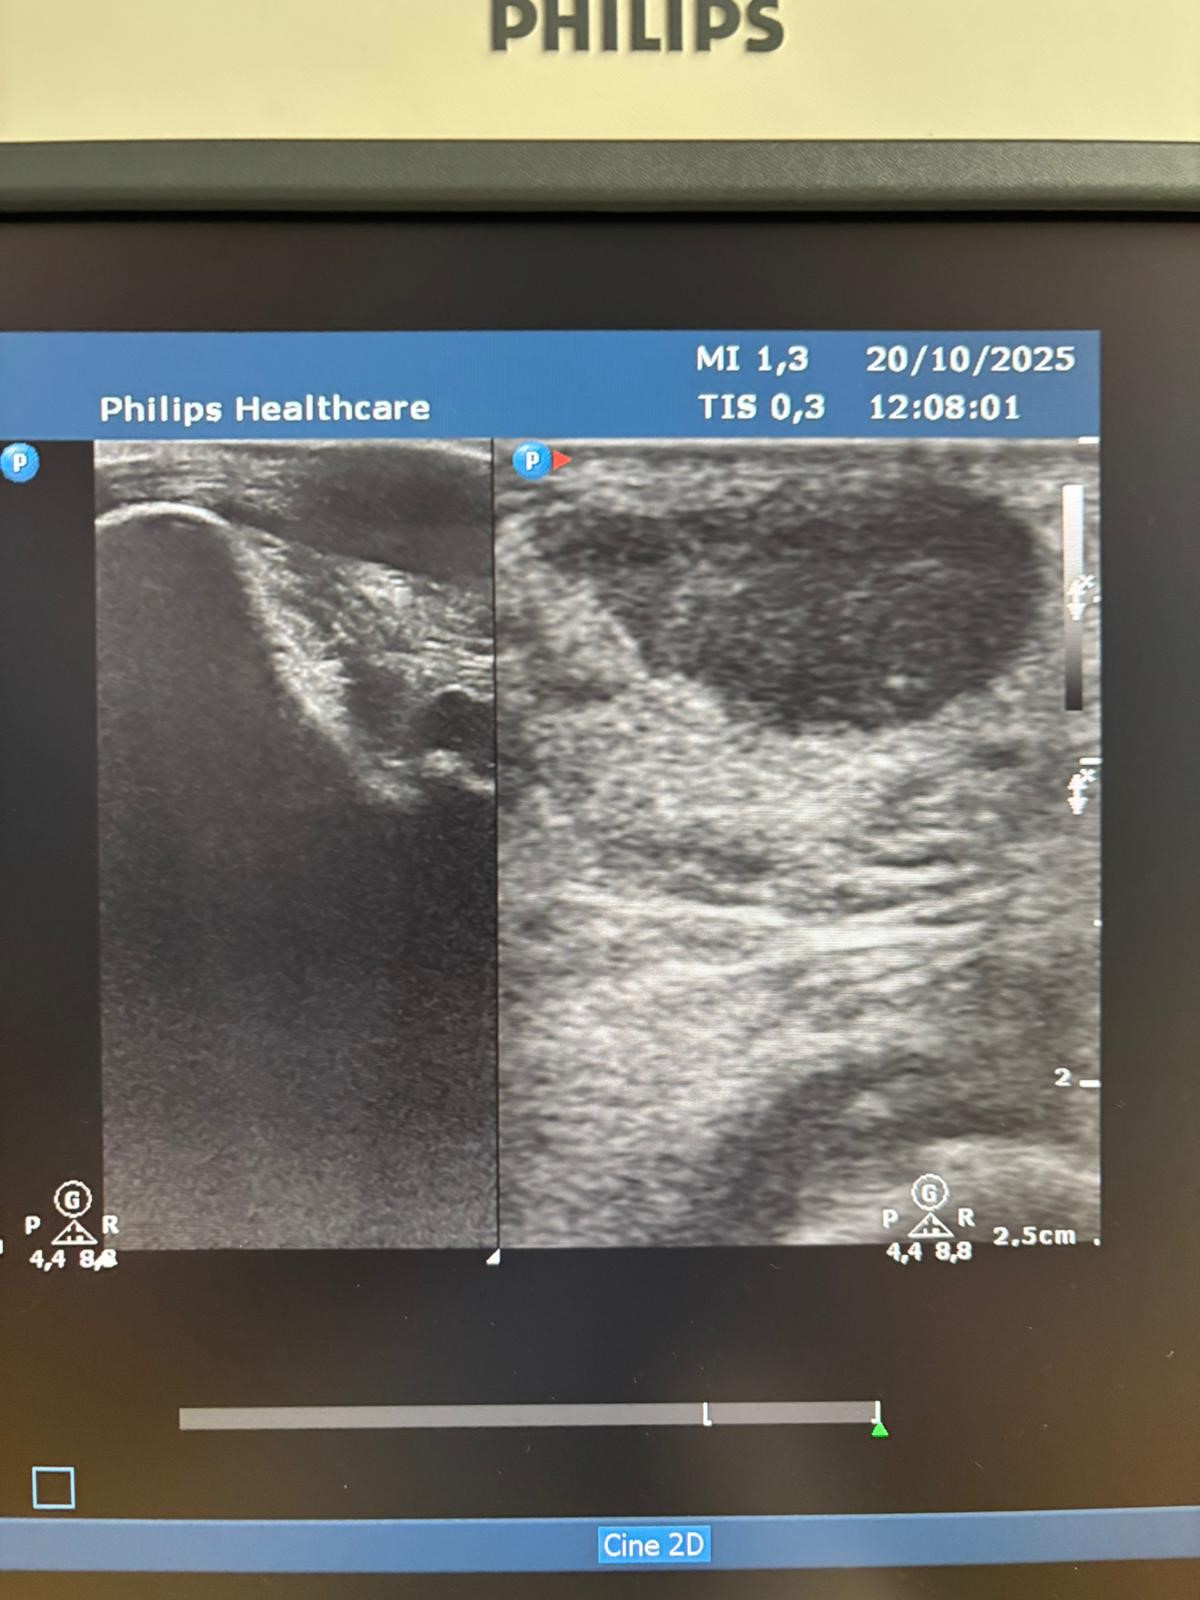

Exploracion Física: deformidad en zona aquílea izquierda. Prueba de Thompson positiva. Decido eco clínica sobre la zona.

Hallazgos ecográficos

ECO clínica: Area hipoecogénica en zona de dolor sospechosa de rotura completa del tendón de aquiles a nivel tercio medio/tercio distal.